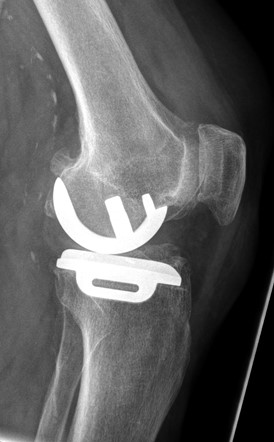

- Röntgenaufnahmen zur Kontrolle des operierten Kniegelenks zeigen eine unverändert regelgerechte Position der Teilprothese (Abb. 7a und 7b)

Abb. 7a und 7b